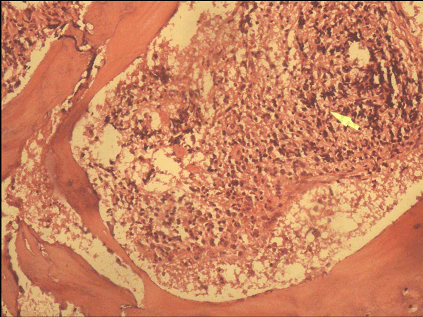

A 14-years-old female child, already a documented case of Down's syndrome proved on cytogenetic analysis, presented to our institute with fever of five days duration associated with bleeding from nose and mouth. Clinical examination of the patient revealed features of Down's syndrome like short stature, macroglossia, low set ears, simian crease and delayed milestones. Abdominal examination revealed palpable splenomegaly two cm below the costal margin. There was no hepatomegaly. Her hematological parameters showed hemoglobin of 3.2 g/dl, total leukocyte count of 3x103/mm3 with normal differential count and platelet count of 2x105/mm3. Examination of blood film did not reveal any immature cells. Erythrocyte sedimentation rate was 84 mm/1st hr. The biochemical parameters were within normal range. She was subjected to bone marrow examination. Bone marrow aspiration revealed a dry tap. Bone marrow biopsy revealed a hypocellular marrow showing presence of granulomatous inflammation consisting of epithelioid cells, Langhan's giant cells, lymphocytes and plasma cells with central areas of caseation necrosis (Figure 1, 2). Ziehl-Neelsen (ZN) staining for AFB was positive. Areas of marked fibrosis with pockets of increased number of megakaryocytes and fibroblasts were present. Reticulin stain showed increased bone marrow reticulin fibres (Figure 3), thus supporting the diagnosis of myelofibrosis. There was no evidence of any leukemic involvement. Since the patient hailed from tuberculous endemic area, diagnosis of myelofibrosis secondary to tuberculosis was contemplated. The patient was put on a course of antitubercular treatment (ATT). Unfortunately she was lost to follow up; therefore repeat bone marrow biopsy could not be done to assess the course of the disease.

Figure 3: Bone Marrow biopsy showing increased bone marrow reticulin fibres (Gomori-methamine silver, x100).